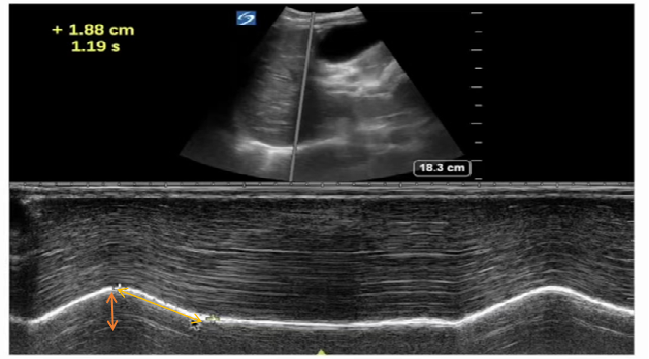

正常人膈肌收缩速度(1.4±0.4)cm/s,运动幅度:1.88 cm(图15)

膈肌收缩速度:1.88/1.19 = 1.57 cm/s。

图片

图15  正常人膈肌收缩速度